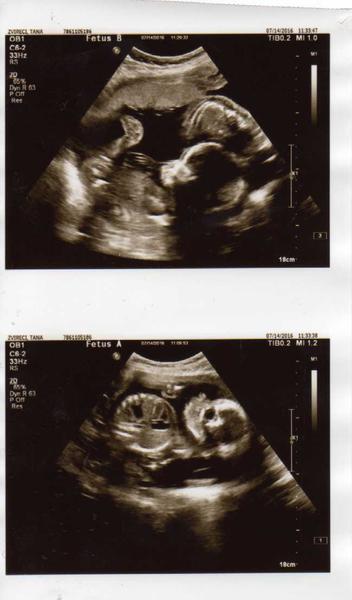

Ahoj holky, tak včerejší 2 screening dopadl moc dobře děti jsou podle uz v pořádku a výpočet rizika se mi snížil. Do třetice potvrzeny holčičky a jedna váží 369g a druhá 337g.